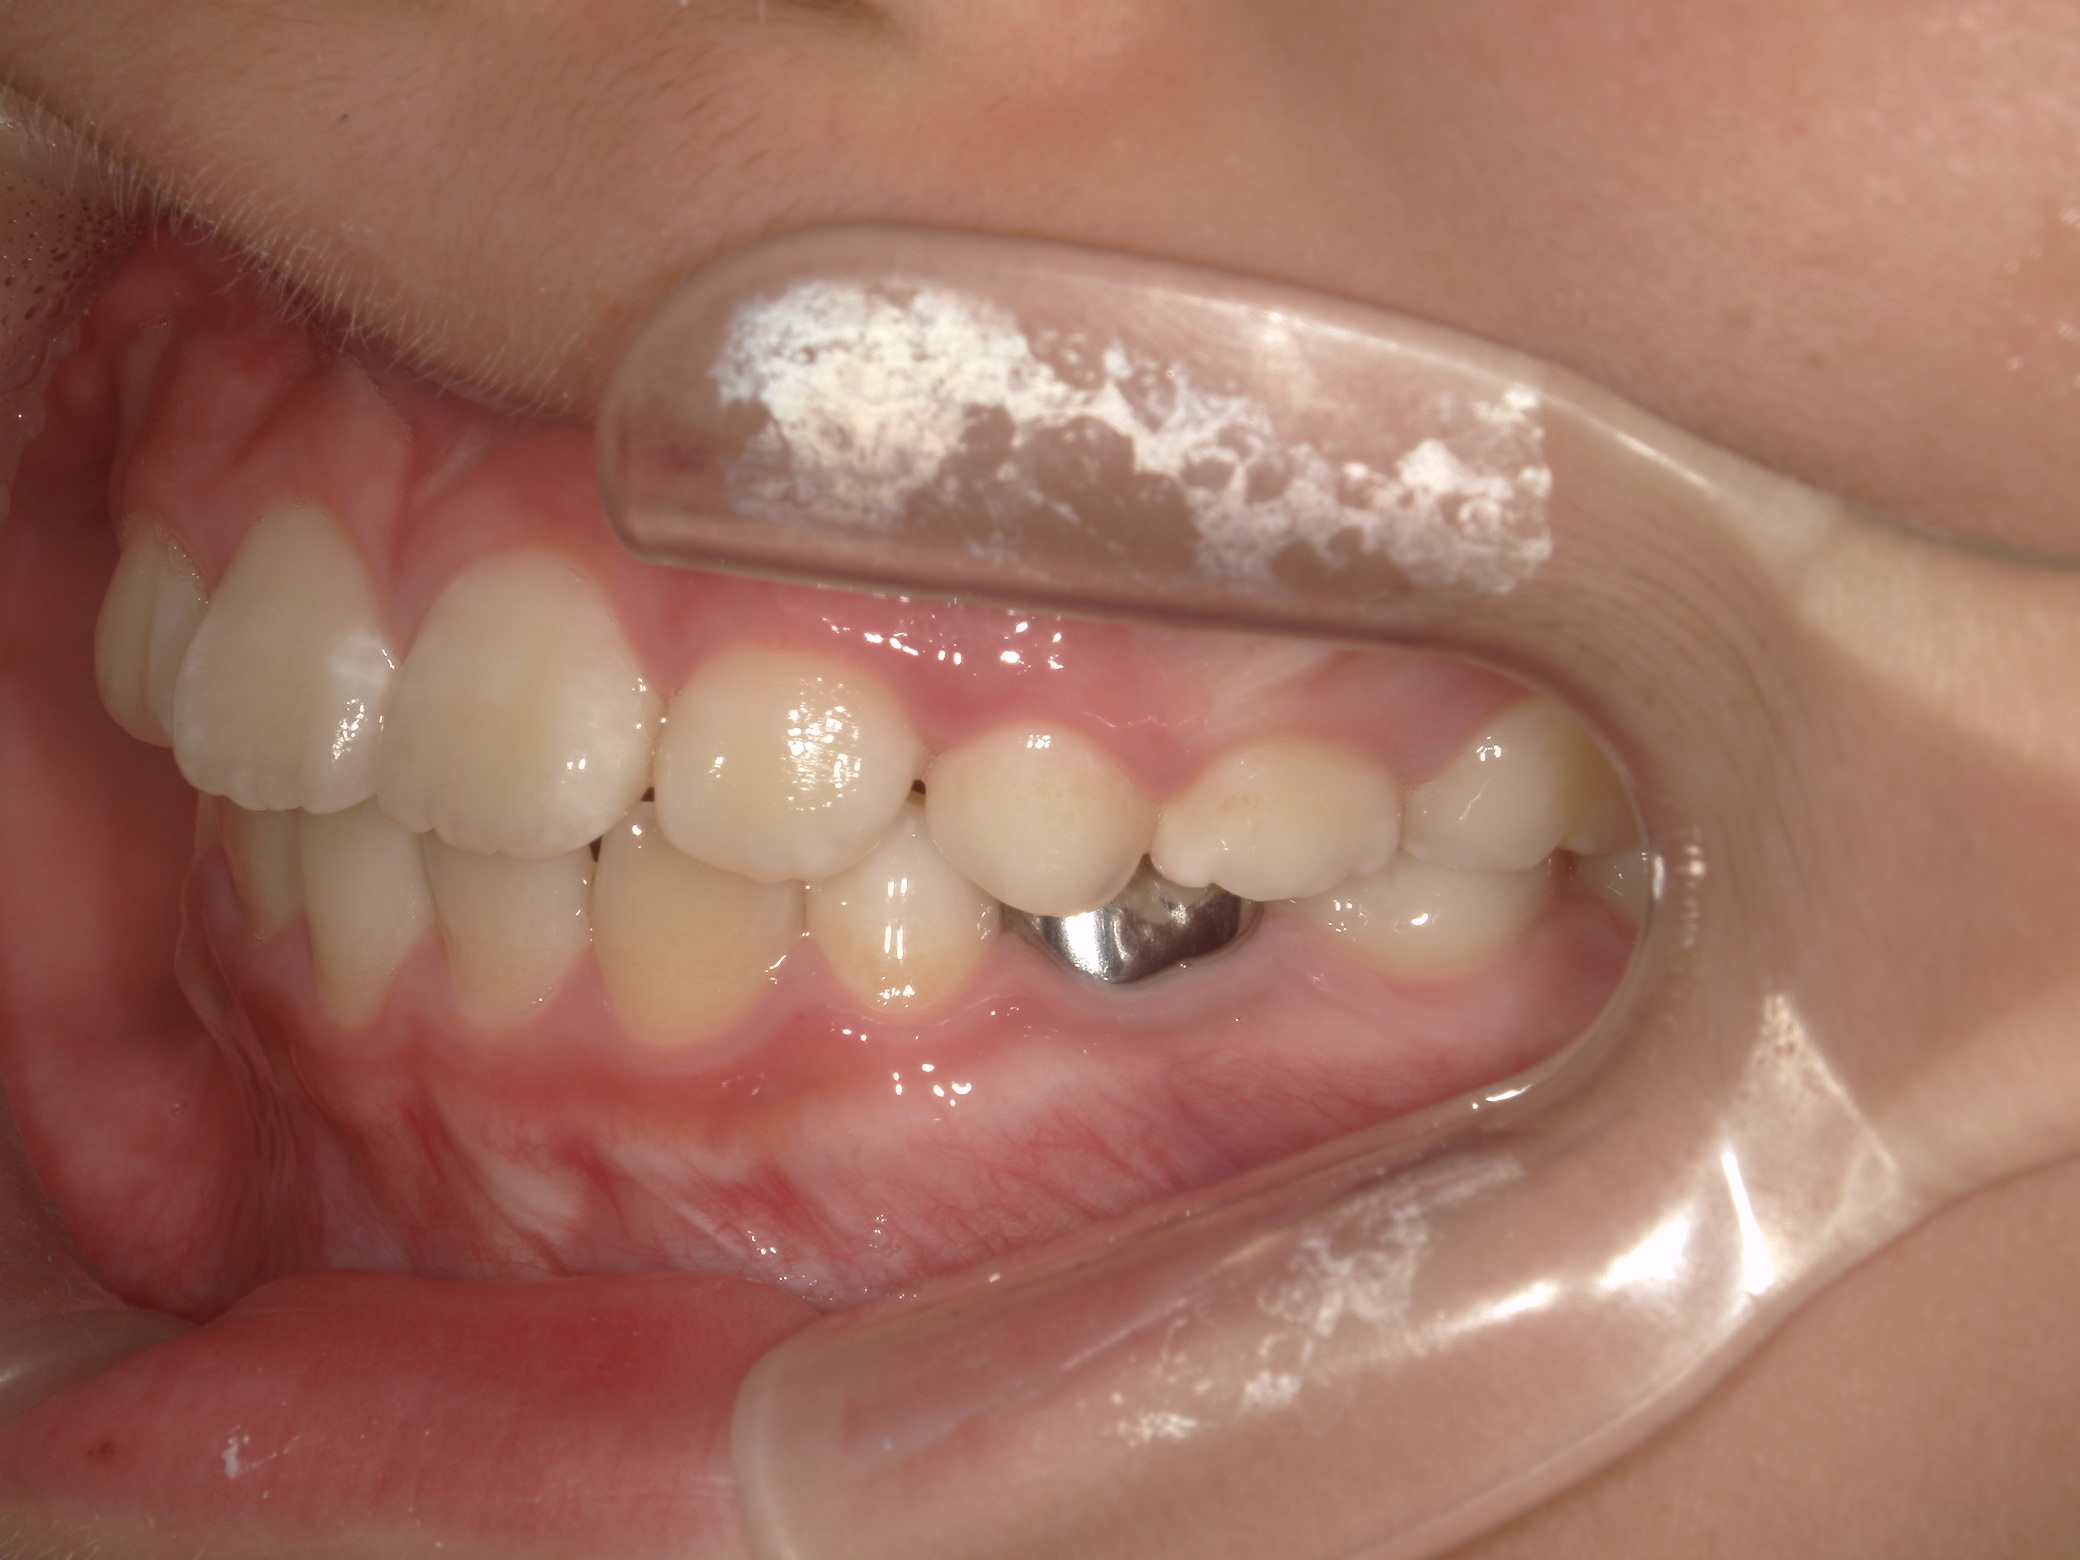

【小学生】マイオブレース矯正 反対咬合(受け口)を改善

小学生で開始

マイオブレース

受け口

非抜歯

1期治療のみで改善

Before

After

治療期間

1.6年

治療開始

8歳

種類

マイオブレース矯正

使用装置

機能矯正装置

コメント

装置装着と 筋機能療法をきっちり取り組んでくれましたので

スムーズに治りました。

現在も安定して 後戻りしていません。